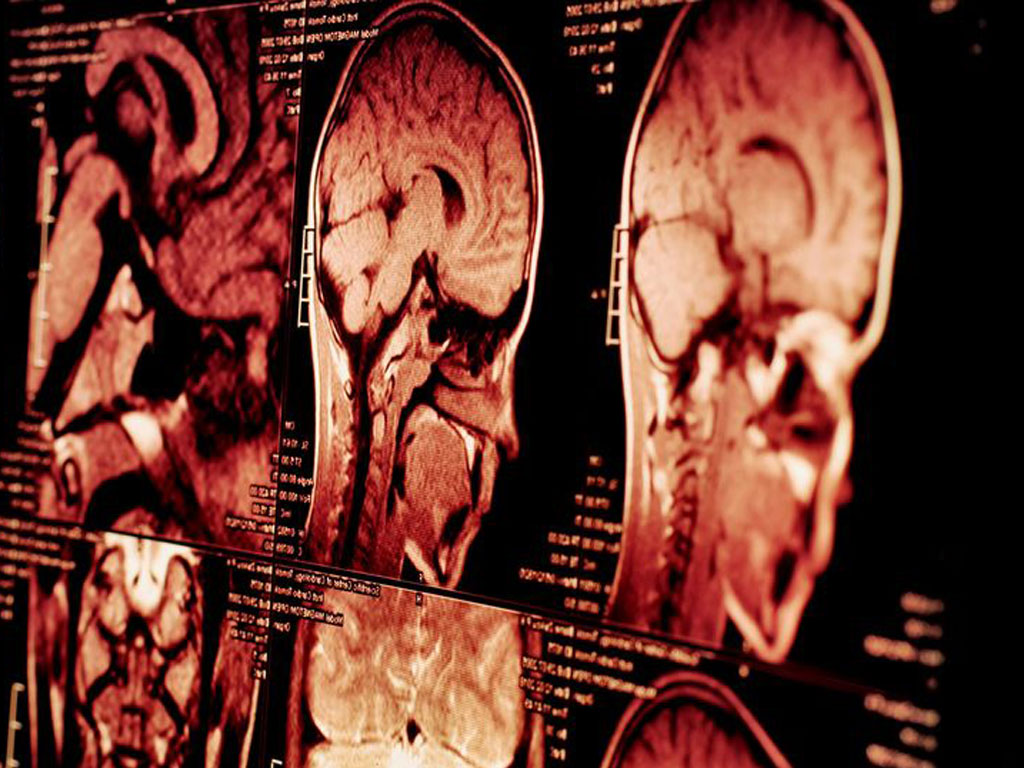

Хотя основной фокус исследования был на IQ, учёные также использовали МРТ-сканирование для части выборки (около 5 000 детей). Было обнаружено, что у детей из социально неблагополучных районов наблюдалось уменьшение толщины коры в лобных и теменных зонах, которые связаны с планированием, вниманием и абстрактным мышлением. Эти структурные особенности коррелировали со снижением IQ на 4–7 баллов.

Доктор Дивьянгана Ракеш из Лондонского института психиатрии пояснила:

«Мы видим не просто статистическую зависимость, а биологический след неравенства, который формируется ещё до подросткового возраста».